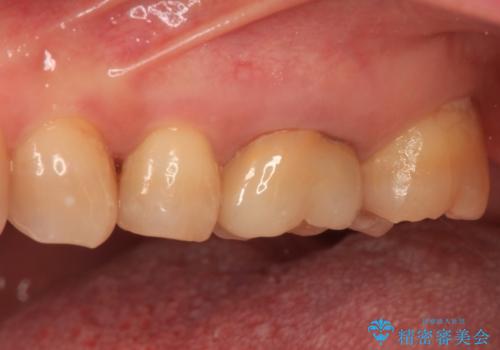

境目にものが詰まって気になる オールセラミッククラウン治療

- 奥歯に装着したクラウンの周りに汚れが溜まりやすいとのことで来院された患者様です。

既に装着されているクラウンの質は決して悪いものではありませんでしたが、患者様自身が非常に気にしていたため、作り替えの治療を行うこととしました。

クラウン装着後は、特にものが挟まる感覚もなく、快適に過ごすことができるようになりました。